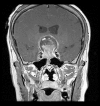

BACKGROUND Pituitary macroadenoma is a common benign tumor that usually presents with visual field defects or hormonal abnormalities. Cerebral infarction can be a complication of a large pituitary adenoma. We report a rare case of bilateral anterior cerebral arteries infarcts by a large pituitary macroadenoma with apoplexy. CASE REPORT A 48-year-old male patient presented with altered conscious level and sudden loss of vision for one-day duration. Magnetic resonance imaging of the brain showed a large seller and suprasellar hemorrhagic mass of pituitary origin, with associated bilateral areas of diffusion restriction in the frontal parasagittal regions, consistent with infarctions. Magnetic resonance angiography showed elevation and compression of A1 segment of both anterior cerebral arteries by the hemorrhagic pituitary macroadenoma. The patient underwent trans-sphenoidal resection of the pituitary adenoma, but unfortunately, ischemia was irreversible. Computed tomography (CT) done post-operatively showed hypodensity in the frontal and parietal parasagittal areas, which was also persistent in the follow up CT scans. The patient's neurological function remained poor, with GCS of 8/15, in vegetative state. CONCLUSIONS Vascular complications of the pituitary apoplexy, although uncommon, can be very severe and life threatening. Early detection of vascular compromise caused by hemorrhagic pituitary macroadenoma can prevent delay in intervention. Clinicians should also consider pituitary adenoma as a possible cause of stroke.